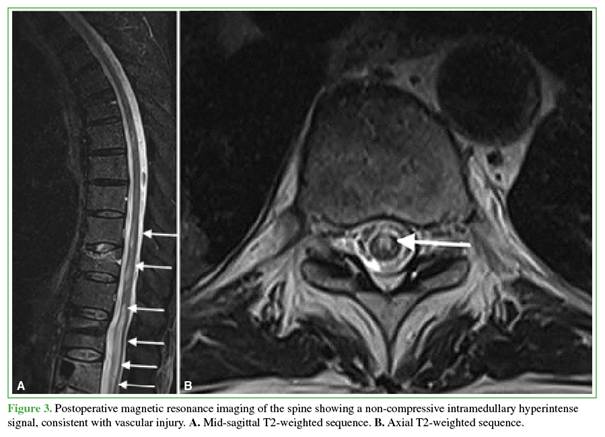

Forty-eight hours after the initial surgery, an emergency spinal magnetic resonance imaging study revealed non-compressive intramedullary hyperintensity consistent with extensive spinal cord ischemia extending from T9 to L4 (Figure 3). The condition was considered a spinal cord injury not amenable to surgical management; therefore, anticoagulation therapy was restarted and the patient was referred to an intensive rehabilitation center.

Spinal cord infarction is an infrequent neurosurgical complication but is associated with extremely high morbidity. We report the case of a 68-year-old man with multiple cardiovascular and oncological comorbidities (active lung and prostate cancer) who developed rapidly progressive acute paraplegia following percutaneous bone biopsy, percutaneous fixation, and bipedicular kyphoplasty at L1. Although computed tomography ruled out mechanical causes and cement leakage, magnetic resonance imaging confirmed spinal cord ischemia extending from T9 to L4. This report analyzes the multifactorial etiology of the event, highlighting the interaction between paraneoplastic hypercoagulability and the surgical technique as key factors to be considered during preoperative planning.